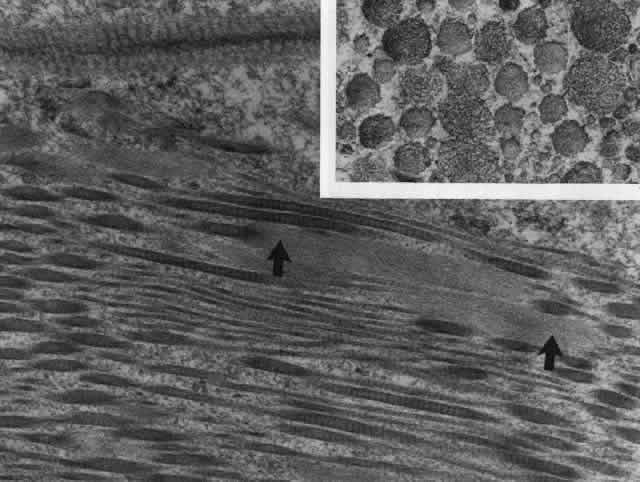

Fig. 24. Electron micrograph of scleral stroma at the periphery of an ulcer in necrotizing

scleritis (same patient as in Figure 23) showing swelling and unraveling of collagen fibrils (arrows) in longitudinal

section (X29,270) and in transverse section (inset, X44,000). Fibrils

of all diameters are affected. (Watson PG, Young RD: Changes at the periphery of a lesion necrotizing

scleritis: Anterior segment fluorescein angiography correlated with electron

microscopy. Br J Ophthalmol 69:656–663, 1985) Fig. 24. Electron micrograph of scleral stroma at the periphery of an ulcer in necrotizing

scleritis (same patient as in Figure 23) showing swelling and unraveling of collagen fibrils (arrows) in longitudinal

section (X29,270) and in transverse section (inset, X44,000). Fibrils

of all diameters are affected. (Watson PG, Young RD: Changes at the periphery of a lesion necrotizing

scleritis: Anterior segment fluorescein angiography correlated with electron

microscopy. Br J Ophthalmol 69:656–663, 1985)

|